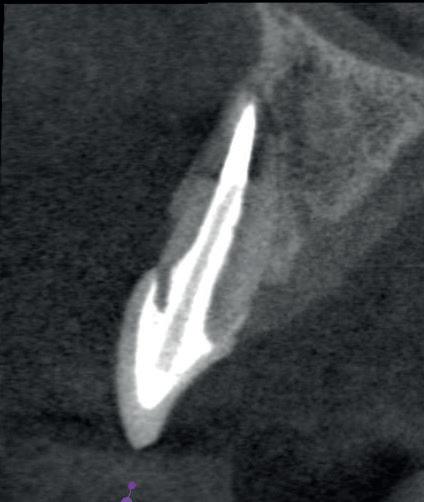

4: Horizontale doorsnede CBCT met radiolucentie mesiopalatinaal van de 11

Er wordt een CBCT gemaakt die een laesie aan de mesiopalatinale zijde van 11 laat zien (afbeelding 4).

15: Horizontale doorsnede CBCT laat bot ingroei zien

16: Sagittale doorsnede CBCT

Bij de controle na 3 jaar (afbeelding 13) is de pocketdiepte verder afgenomen tot 4 mm (afbeelding 14), de gingiva is stevig en er is geen bloeding na sonderen. De CBCT laat duidelijk ingroei van het bot zien (afbeelding 15 en 16). De laatste röntgenfoto dateert van 14 jaar na de behandeling (afbeelding 17), er zijn geen klachten en de parodontale conditie is stabiel.